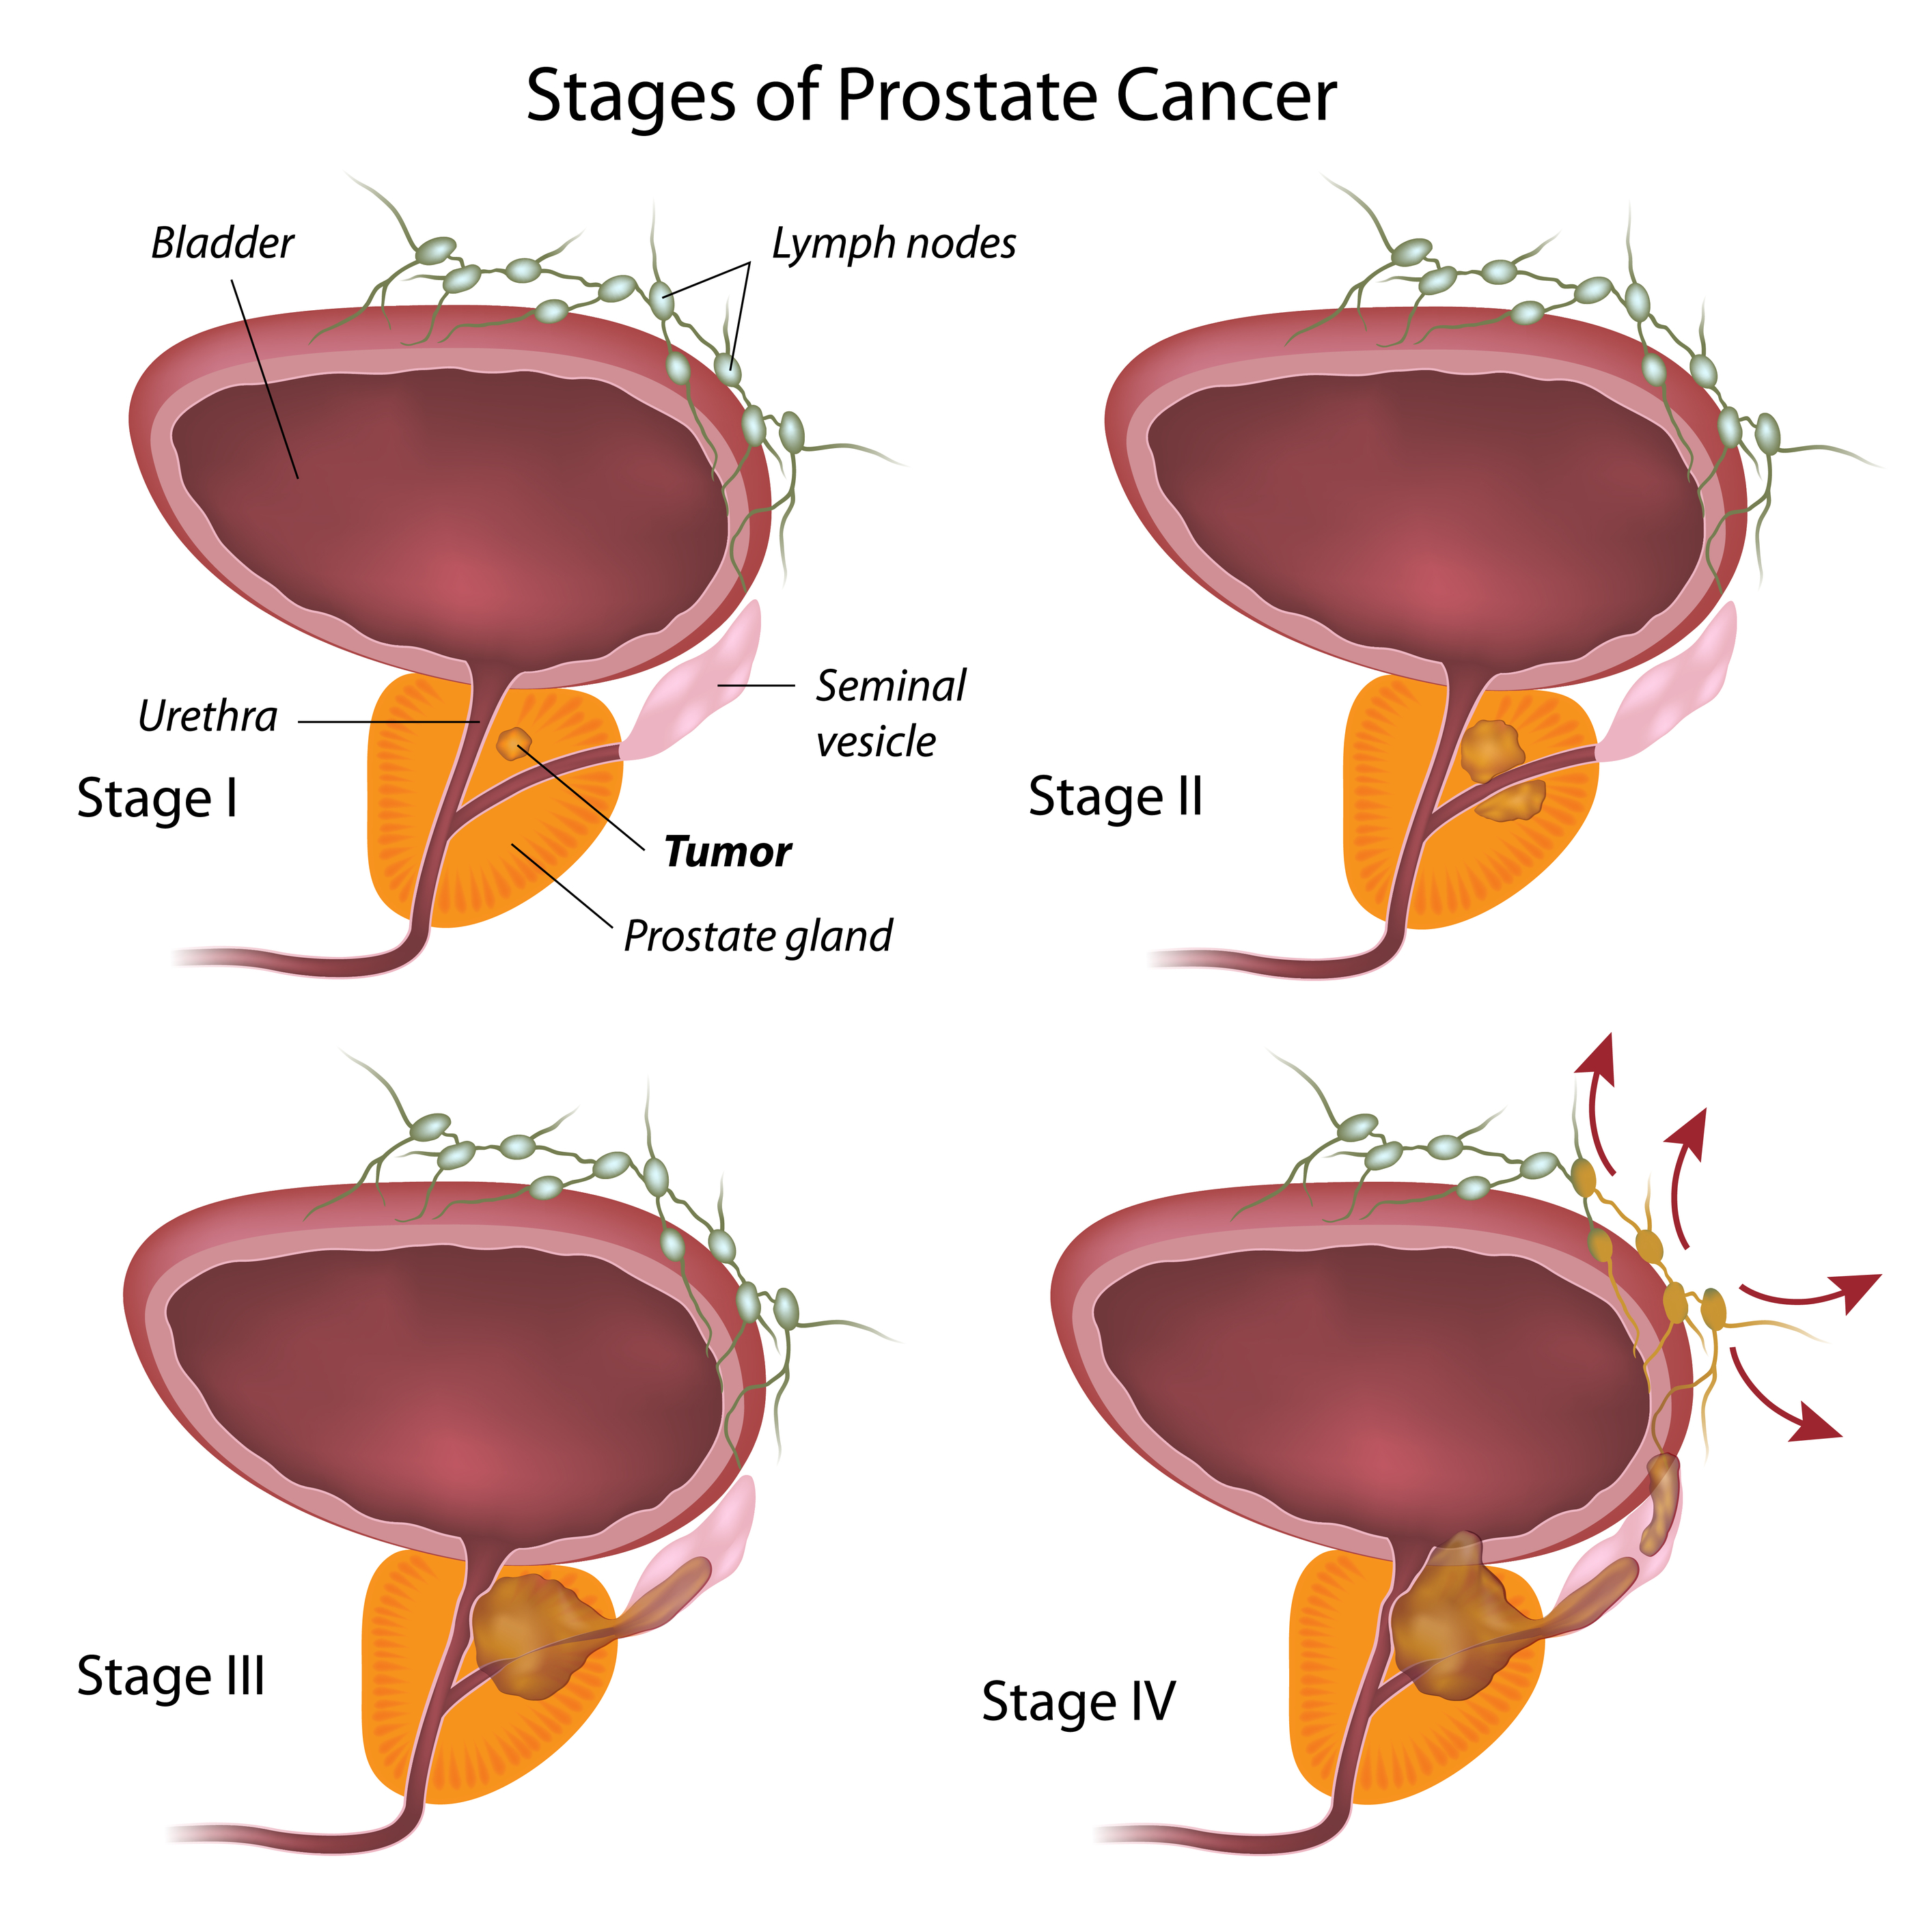

Prostate Cancer Stages – University Health News

Staging and grading | Early prostate cancer – Macmillan Cancer Support

A generalized overview of prostate cancer (PCa) progression …